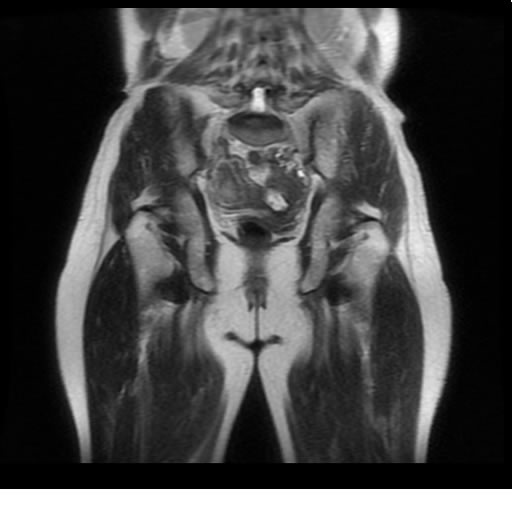

Se realizan adquisiciones en diferentes planos, con secuencias Spin echo y GRE, ponderadas a T1 y a T2, se utilizan pulsos de saturación de grasa y se administra medio de contraste a base de gadolinio.

El útero está en retroversión, retroflexión, y en posición central, se observa liquido en la cavidad endometrial, debido a la presencia de un Ca endometrial; en el anexo derecho se observa una masa quística que mide 3.8 x 2.2 cm de diámetro, corresponde a un quiste bilobulado, posee pared gruesa con componente solido puede tratarse de un Cistoadenocarcinoma, el cual realza con el medio de contraste de forma importante, entra dentro de una clasificación O-Rad tipo IV compatible con un Cistoadenocarcinoma

O-RAD tipo IV, Cistoadenocarcinoma